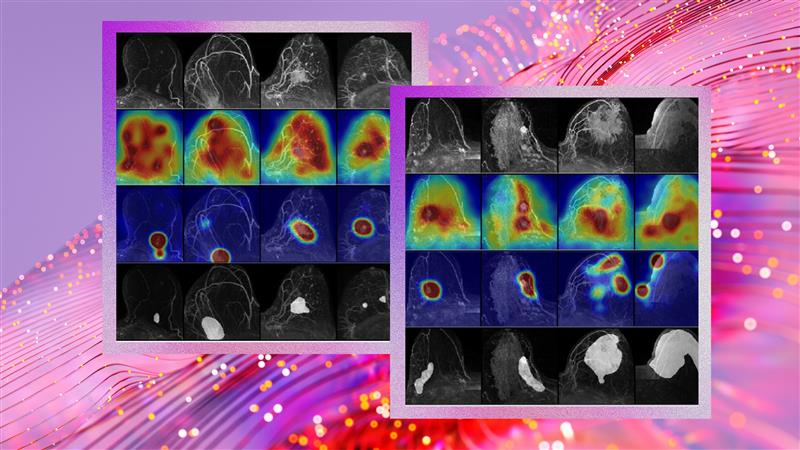

Exceptional Explainability:

Unlike “black box” systems, FCDD produces heatmaps that highlight exactly where the tumor may be located in the MRI. These AI-generated maps corresponded with expert radiologist annotations in 92% of cases (pixel-wise AUC), putting explainability at the forefront of clinical trust. -

FCDD’s heatmaps make AI’s “thought process” visible, helping radiologists make more informed decisions and patients to better understand their diagnosis.